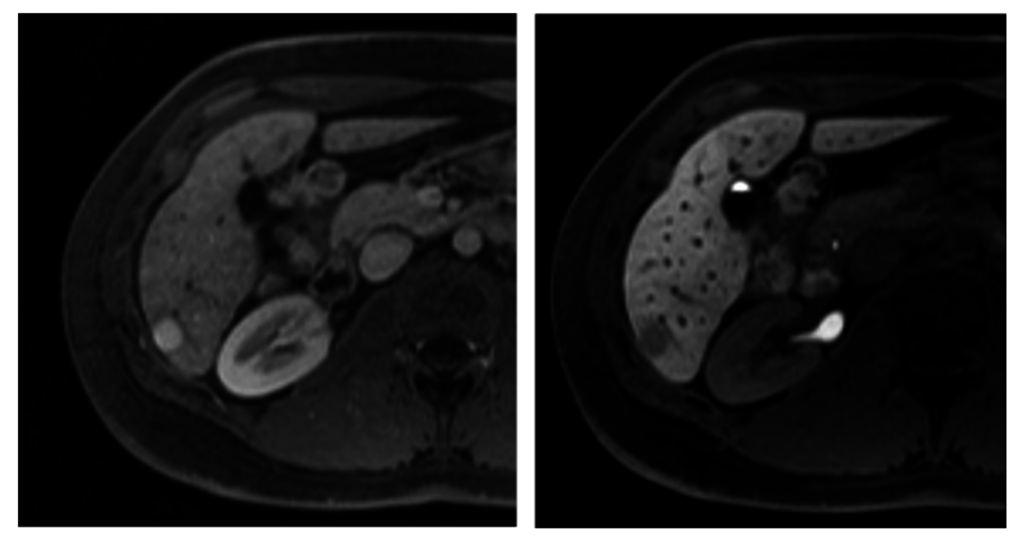

3.2. Diffusion-Weighted MR Imaging

3.3. Dynamic Contrast Enhanced MRI